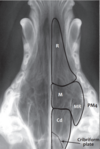

Review normal anatomy.

Dotted line – cribriform plate

What do you see?

Nasal chambers R – rostral part - Numerous slightly wavy parallel lines. M – middle part. Rounded, more widely spaced lines. Cd – caudal part. Linear lines.